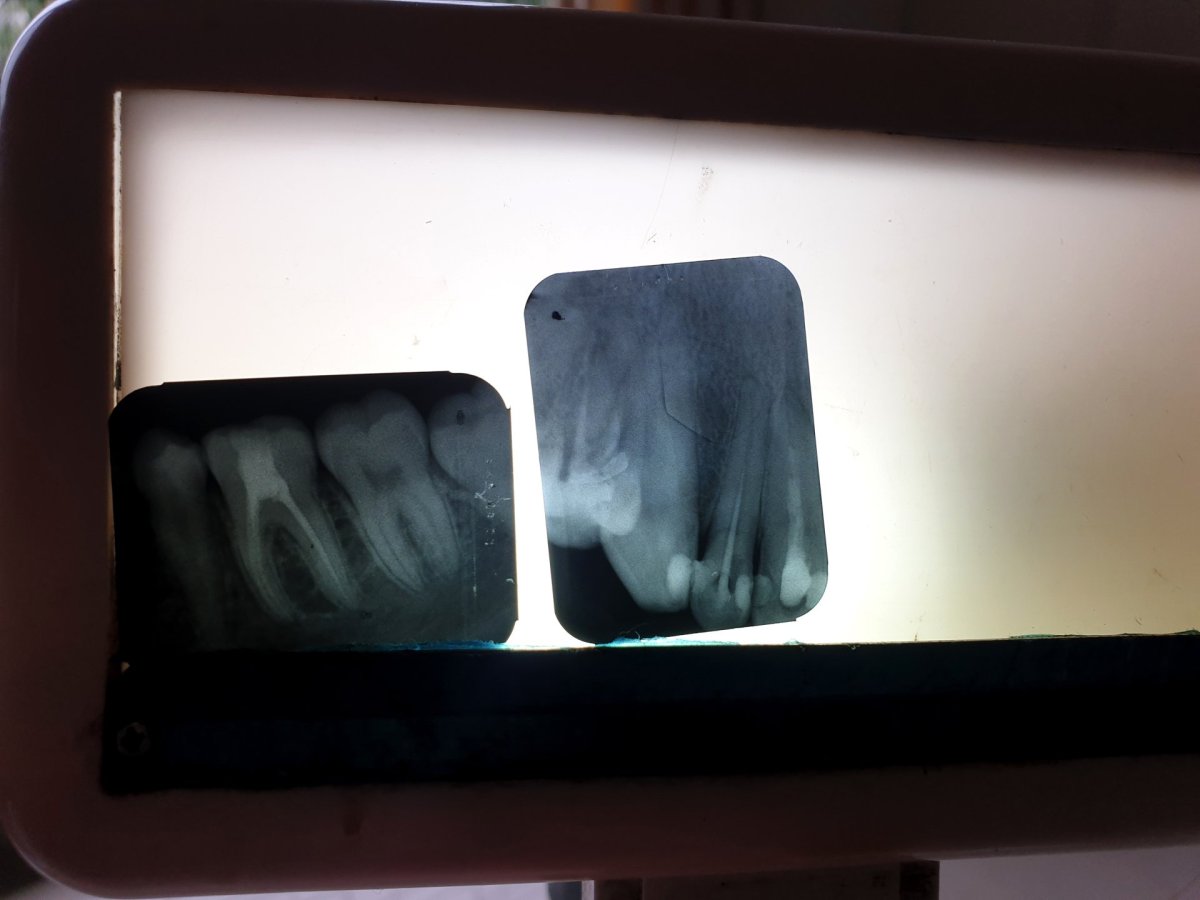

Na rentgenovém snímku mi ukázal, že po odstranění kazu nedošlo k úplnému vyplnění dutiny a kaz se znovu začal šířit. I přes trošku neortodoxní praktiky, jako třeba ponechání zubu otevřeného dva dny, které jsem konzultoval vzdáleně se svým známým, jenž má soukromou dentální ordinaci v Praze a za smějícími se smajlíky byly dobře rozpoznatelné jeho protáčející se oči, jsem byl po třech návštěvách, rozložených do jednoho týdne, spokojený. Zubařovo vychvalování svého umu, který si v ničem nezadá s evropskými kolegy, i mírný nátlak na "pět hvězdiček" v recenzi jeho kliniky bych mu klidně odpustil.

Rentgenové snímky jasně ukázaly chybně provednou výplň horního řezáku a další kaz na spodní stoličce